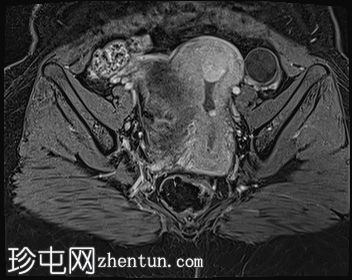

轴位

DWI序列

子宫体积增大,宫底可见息肉样病变,T2加权像呈异常中高信号强度。病变可见轻度扩散受限,增强后呈均匀强化。病变与宫底交界区之间可见一界限清晰的异常高T2信号区域,可能为囊性变性。未见病变超出交界区。

在剖宫产切口远端的前壁上,可见另一处类似的较小病灶。

左侧附件囊性病变,T1加权像信号异常低,T2加权像信号异常高。无增强扫描强化。

子宫内膜息肉是子宫内膜组织的结节状突起。通常表现为T2加权像信号异常高,增强扫描后呈均匀强化。

病理检查通常显示增生期子宫内膜紊乱。